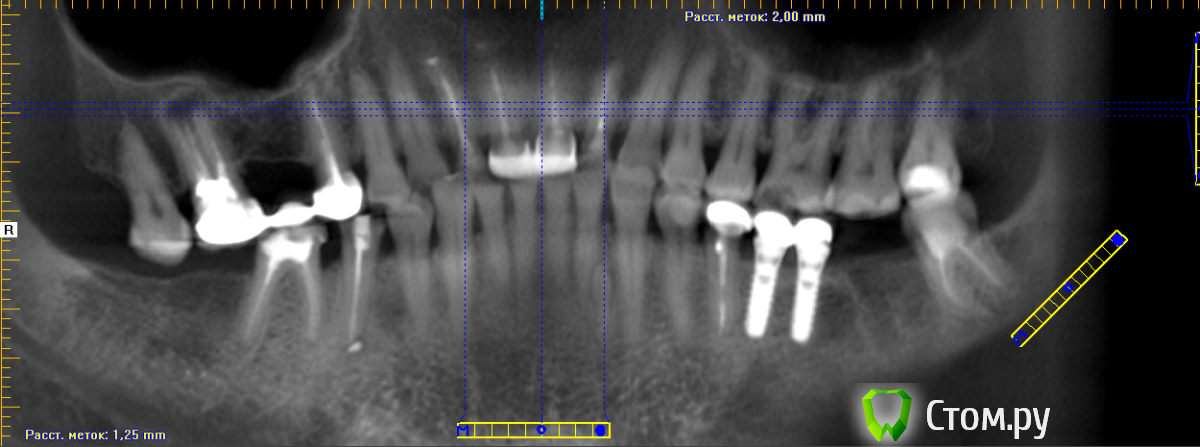

Konstantin88 Опубликовано 24 июня, 2014 Поделиться Опубликовано 24 июня, 2014 Уважаемые доктора!!!!помогите пожалуйста определить систему имплантации по КТ , может быть кто нибудь узнает.Пациент ставил их около 6 лет назад, доктор который устанавливал уехал в США, информации в карте нет. Ссылка на комментарий

ILGAMSA Опубликовано 24 июня, 2014 Поделиться Опубликовано 24 июня, 2014 Уважаемые доктора!!!!помогите пожалуйста определить систему имплантации по КТ , может быть кто нибудь узнает.Пациент ставил их около 6 лет назад, доктор который устанавливал уехал в США, информации в карте нет.Безымянный.pngШтрауманн Ссылка на комментарий

Konstantin88 Опубликовано 24 июня, 2014 Автор Поделиться Опубликовано 24 июня, 2014 Штрауманнбез сомнений? Ссылка на комментарий

Konstantin88 Опубликовано 24 июня, 2014 Автор Поделиться Опубликовано 24 июня, 2014 ILGAMSA спасибо большое сейчас нашел снимки в яндексе да они эдентичны Ссылка на комментарий

johniola Опубликовано 24 июня, 2014 Поделиться Опубликовано 24 июня, 2014 штрауманн Ссылка на комментарий

Mane Опубликовано 26 июня, 2014 Поделиться Опубликовано 26 июня, 2014 Ильгамса бьет точно в цель! Ссылка на комментарий